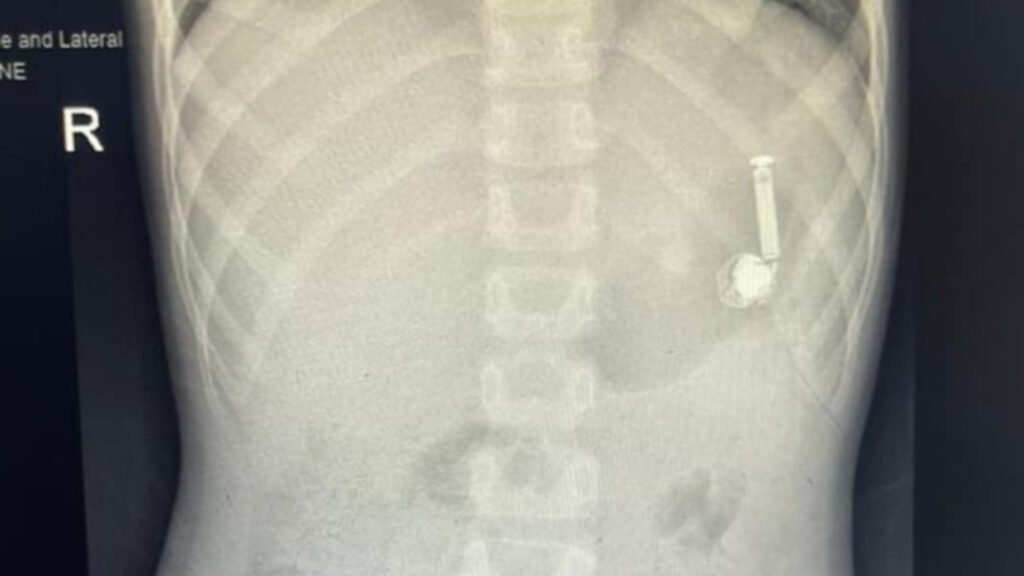

ಅಗತ್ಯ ವೈದ್ಯಕೀಯ ಪರೀಕ್ಷೆಗಳು ಮತ್ತು ಕ್ಷ-ಕಿರಣಗಳನ್ನು ಮಾಡಲಾಯಿತು. ಎಂಡೋಸ್ಕೋಪಿ ವಿಭಾಗ ಮತ್ತು ಅರಿವಳಿಕೆ ವಿಭಾಗದಿಂದ ವೈದ್ಯಕೀಯ ತಂಡವನ್ನು ರಚಿಸಿ, ಮಗುವನ್ನು ಎಂಡೋಸ್ಕೋಪಿಗೆ ಸಿದ್ಧಪಡಿಸಲಾಯಿತು. ನಂತರ ಲ್ಯಾಪ್ರೊಸ್ಕೋಪಿ ಮೂಲಕ ಇಯರ್ ಬಡ್ ಹೊರ ತೆಗೆಯಲಾಯಿತು.